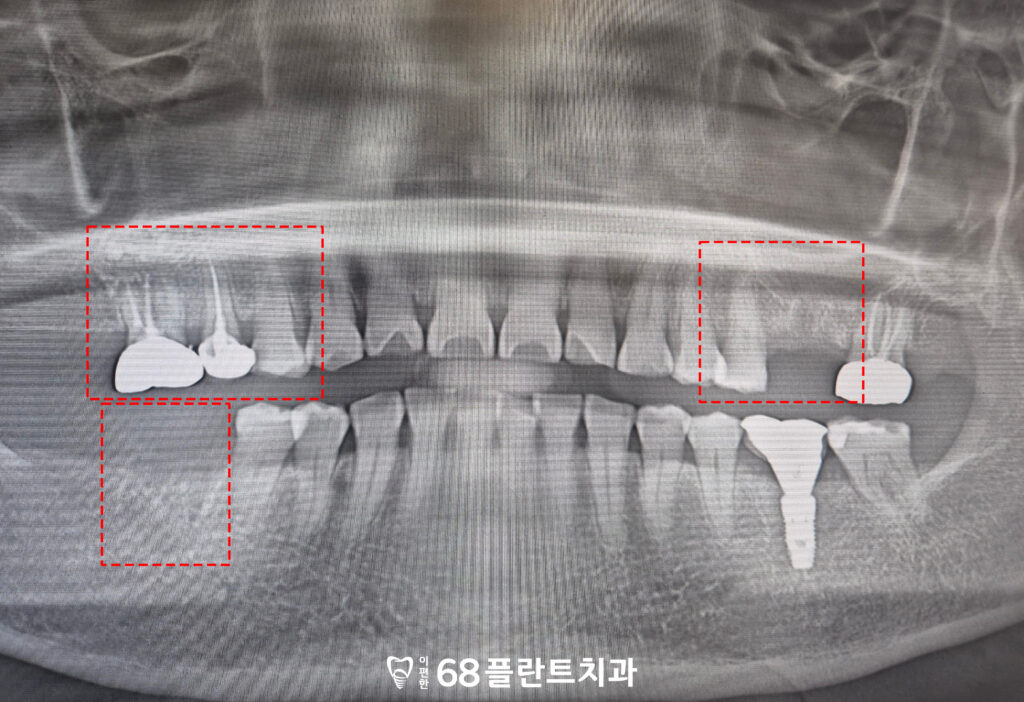

위 환자분은

식사를 할 때 마다 치아가

전체적으로 아프고 불편하다며

광명시치과 이편한68플란트에

내원해 주셨습니다.

확인해 보니,

이미 치아가 상실된 부위가 있었고

여러 치아에는 크랙이 발생해

저작 시 통증과 불편함이

반복되고 있는 상태였습니다.

균열의 진행 정도가 심해

보존이 어려운 치아들은

발치를 결정하였으며,

기존에 치아가 상실된 부위와 함께

임플란트 식립을 진행하기로 계획하였습니다.